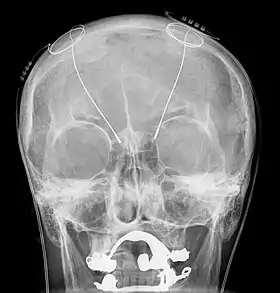

Deep brain stimulation treats intention tremors, but does not help related diseases or disorders such as dyssynergia and dysmetria.[17] Deep brain stimulation involves the implantation of a device called a neurostimulator, sometimes called a "brain pacemaker". It sends electrical impulses to specific parts of the brain, changing brain activity in a controlled manner. In the case of an intention tremor, the thalamic nuclear region is targeted for treatment. This form of treatment causes reversible changes and does not cause any permanent lesions. Since it is reversible, deep brain stimulation is considered fairly safe. Reduction in tremor amplitude is almost guaranteed and sometimes resolved. Some individuals have seen sustained benefits in MS progression.[18]